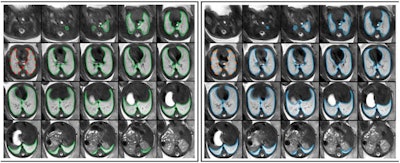

To investigate the reproducibility of radiomics features extracted from 2-D ROIs versus whole-lung (3D) ROIs in repeated in-vivo fetal MRI acquisitions, the team carried out 30 fetal MRI scans, including two axial T2-weighted acquisitions of the lungs; 2D (lung at the level of the carina) and 3D (whole lung) ROIs were manually segmented.

The authors extracted a total of 95 radiomics features from 2 and 3D ROIs in initial and repeat acquisitions. Radiomics feature intra-class correlation coefficients (ICC) were calculated between 2 and 3D ROIs in the initial acquisition, and between 2 and 3D ROIs in repeated acquisitions.

Median radiomics feature ICC between 2 and 3D ROIs in the initial MRI acquisition was 0.733 (interquartile range, 0.313-0.814; range, 0.018-0.970). ICCs between radiomics features extracted using 3D ROIs in initial and repeat acquisitions (median, 0.908 [interquartile range, 0.824-0.929; range, 0.335-0.996]) were significantly higher compared with 2D ROIs (0.771 [0.699-0.835, 0.048-0.965]) (p < 0.001).